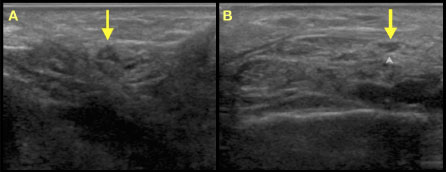

Figure 1: Ultrasonographic images of nerves localized: A) left superficial fibular nerve deep to fascia; B) left sural nerve lateral to Achilles' tendon. View Figure 1

The superficial fibular and sural nerves were targeted based on the distribution of her pain. She reported pre-procedural pain severity of 8/10. The procedure was carried out under sterile technique, utilizing a sterile ultrasound transducer cover and sterile ultrasound gel. Pre-procedural scanning was performed to determine optimal needle approach for the procedure. The patient was prepared and draped in sterile fashion. The skin superficial to each nerve was prepared with sterile chlorhexidine. The skin at the site was then anesthetized subcutaneously with 5 cc of 1% lidocaine, using a 1-inch 25G needle, raising a skin wheal superficial to each nerve. After confirming local anesthesia, a cryoprobe was inserted with ultrasonographic guidance towards the sural nerve lateral to the Achilles tendon and the small saphenous vein. The sterile tip was iteratively inserted, with overlap until the entire treatment area for the sural nerve was completed. The same process was then repeated for the superficial fibular nerve, which was treated approximately 10 cm proximal to the lateral malleolus in the triangle formed by the peroneus brevis and extensor digitorum longus muscles and the overlying fascia.